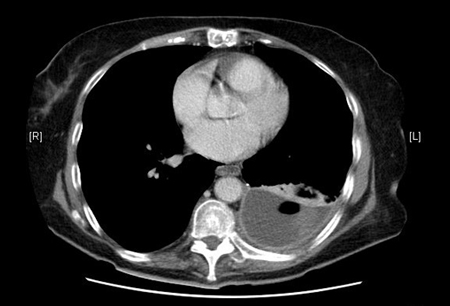

CT scan of thoracic empyema

From the collection of Najib Rahman, RTU, Oxford